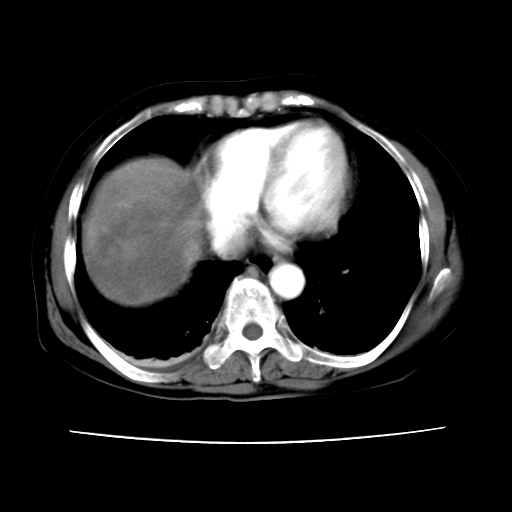

2008-11-10ct平扫(其间去中山医院诊治未行特殊治疗)

2008-11-10ct平扫见并肝内、血膜下血肿基本吸收,肝内低密度灶缩小。此时再做增强ct应有显着意义。对患者/医者都好!

患者自6月至11月,如果是肝癌,没有经过特殊治疗,想必应该会有所进展吧,而不是ct所见,反而似有病灶减小的趋势。建议增强。